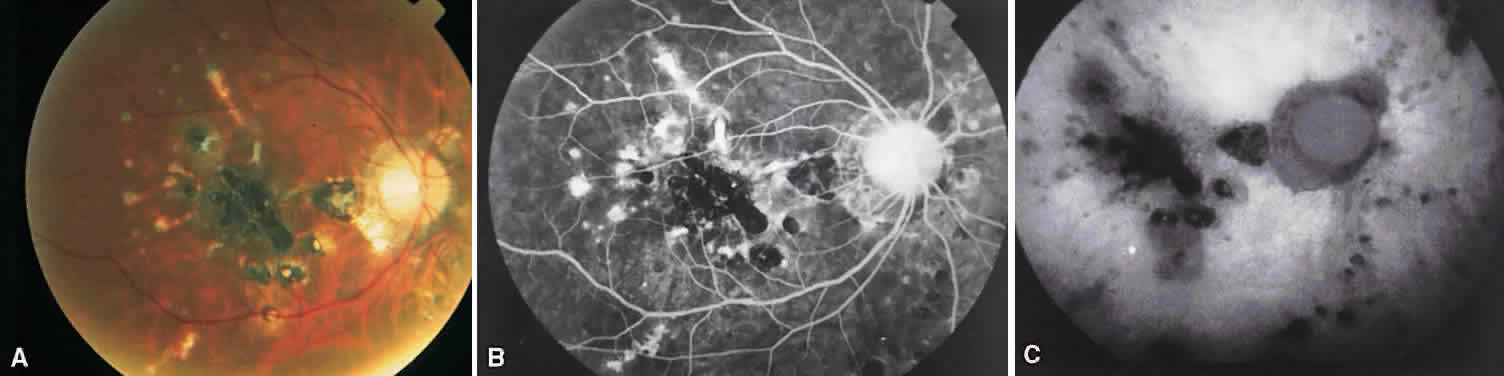

BEHÇET'S DISEASE

Behçet's disease is a systemic occlusive vasculitis that presents predominately in young middle Eastern and Japanese men. The classic features include acute hypopyon, iritis, aphthous stomatitis, and genital ulceration. Skin lesions and strokes also occur frequently. There often is an acute recurrent bilateral panuveitis. Ocular findings include retinal vasculitis (Fig. 6A) with an occlusive arteritis, vitritis, macular edema, ischemic retinitis, ischemic optic neuropathy, peripheral neovascularization, and occasionally SRNV.

Fig. 6. Behçet's disease. A. Fundus photograph showing vasculitis of the superotemporal vascular arcade. Intraretinal hemorrhages also are seen. B. Fluorescein staining of the vessel wall and adjacent areas of blocked fluorescence corresponding to the intraretinal hemorrhage.

On fluorescein angiography (see Fig. 6B), during the active phases of the disease, capillary dropout and dilated retinal capillaries are seen. Dilated retinal capillaries (particularly peripapillary capillaries) leak dye and cause retinal and disc staining.19 Cystoid macular edema,19 SRNV, and disciform scars often are seen.20 Leakage of peripheral capillaries can be seen in patients with normal-appearing fundi.21

ICG angiography shows hyperfluorescent spots from the early to late phases and hypofluorescent plaques, both of which are not evident on FA. Staining of choroidal vessel walls and leakage of ICG from the choroidal vessels also have been described.22–24